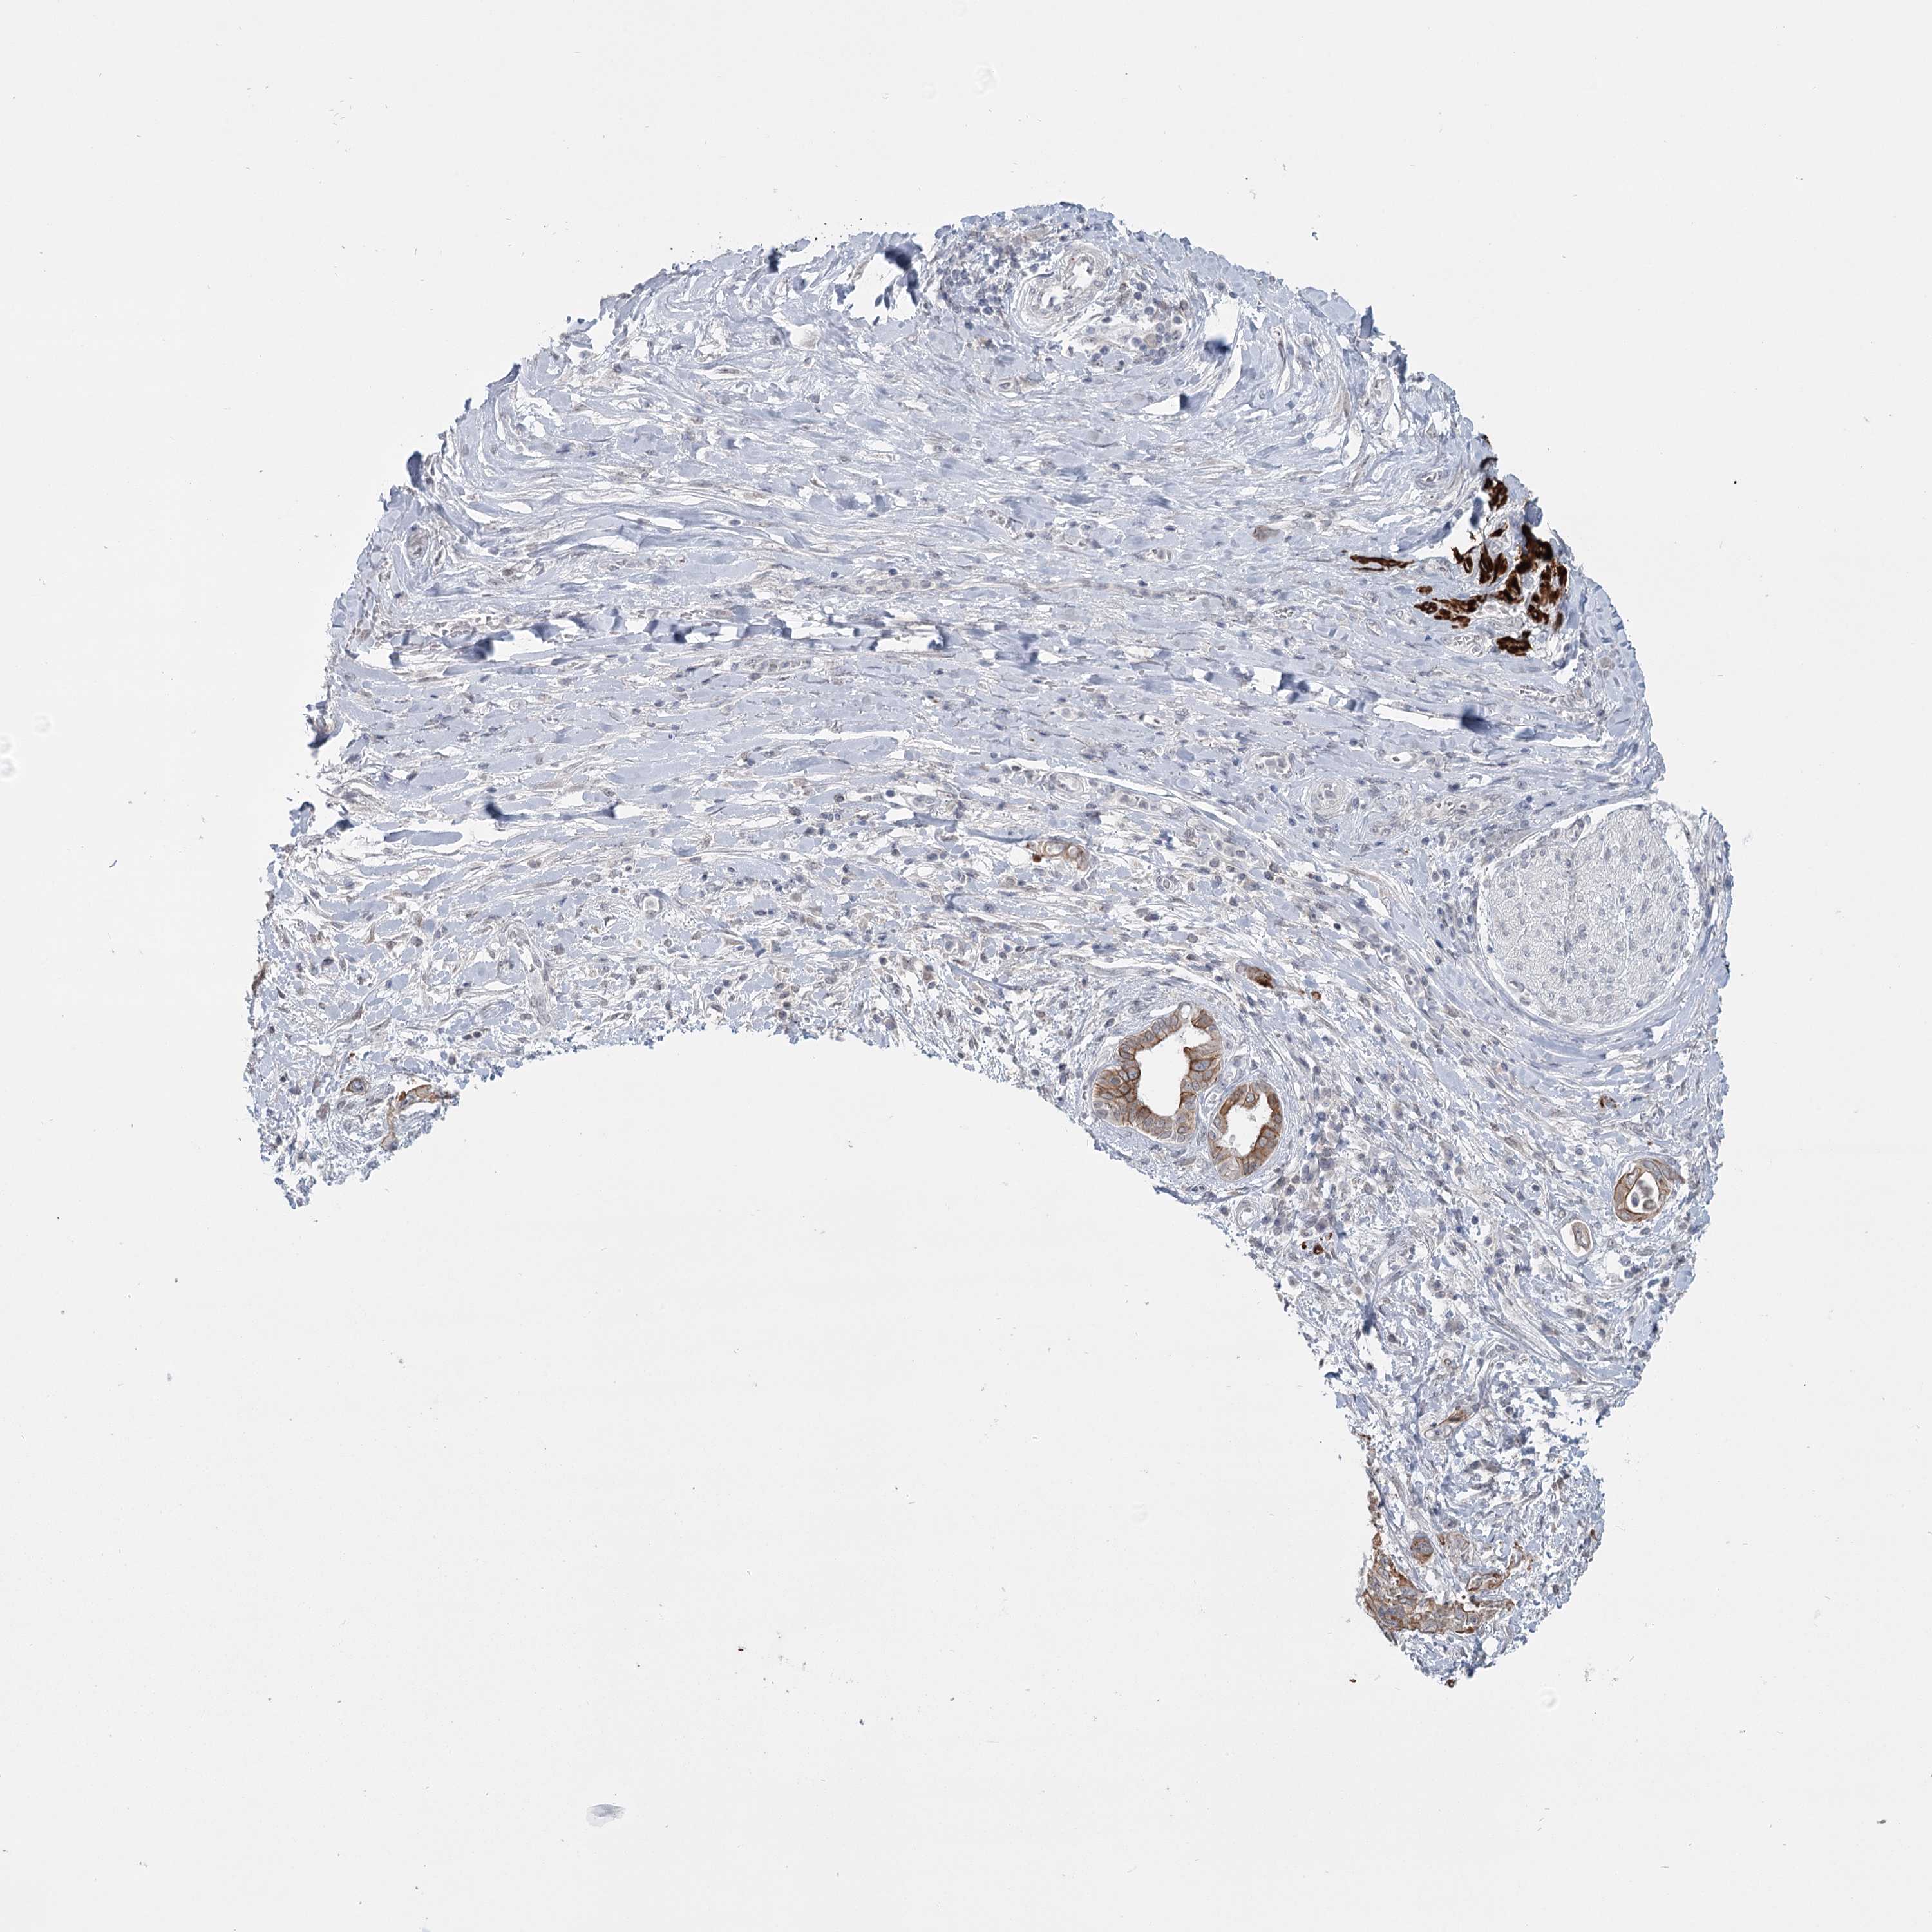

PANCREATIC CANCER - Protein expressioni

A mouse-over function shows sample information and annotation data. Click on an image to view it in a full screen mode. Samples can be filtered based on level of antibody staining by selecting one or several of the following categories: high, medium, low and not detected. The assay and annotation is described here.

Note that samples used for immunohistochemistry by the Human Protein Atlas do not correspond to samples in the TCGA dataset.

Antibody stainingi

Antibody staining in the annotated cell types in the current human tissue is reported as not detected, low, medium, or high, based on conventional immunohistochemistry profiling in selected tissues. This score is based on the combination of the staining intensity and fraction of stained cells.

Each image is clickable and will lead to virtual microscopy that enables deeper exploration of all samples and also displays staining intensity scores, fraction scores and subcellular localization as well as patient and tissue information for each sample.

Antibody HPA023187

Antibody CAB034226

Staining

High

Medium

Low

Not detected

Adenocarcinoma, NOS